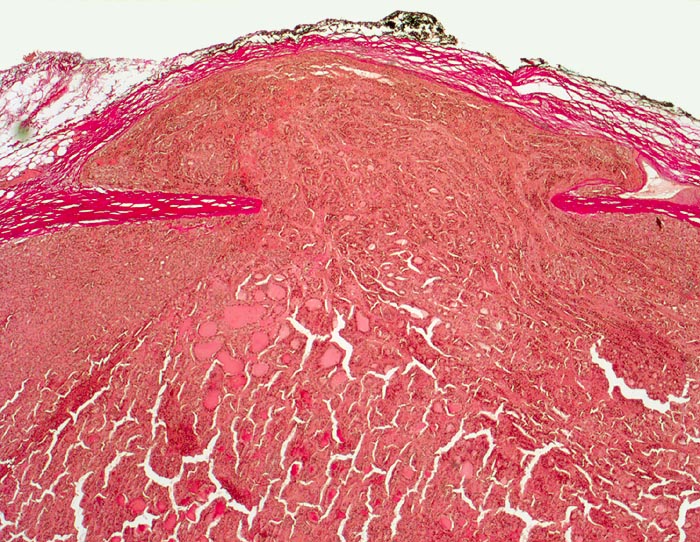

Follikuläres Schilddrüsenkarzinom: Kapseldurchbruch

Follikulärer Tumor mit dicker Kapsel. Der Tumorknoten ist zwar von einer Neokapsel bedeckt, hat aber eine imaginäre Linie entlang der ursprünglichen Kapsel überschritten.

Vor einem Jahr Schilddrüsenteilresektion wegen follikulärem Karzinom. Jetzt Resthyreoidektomie wegen Rezidiv.